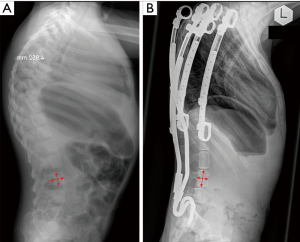

The growth-stimulating effect, commonly documented by a simplified 2-dimensional assessment of T1-S1 or T1-T12 distance on AP radiographs, has repeatedly been confirmed. These measurements, however, are limited by the projectional nature of a spine radiograph and the ignorance of more detailed regional growth phenomenon. We therefore performed a retrospective radiographic study with a minimum 4-year follow-up to further investigate the effect of year-long distraction-based EOS treatment by VEPTR on vertebral growth modulation (19). Two groups of nine patients each with EOS, all displaying normally segmented and shaped lumbar vertebrae at the beginning of VEPTR treatment were compared. Group 1 consisted of patients with VEPTR constructs spanning the lumbar spine, whereas patients in group 2 all had VEPTR constructs leaving the lumbar spine uninstrumented. Although the gain in vertebral body height (VBH) of the lumbar segments did not differ significantly between groups, patients in group 1 had significantly less growth in regards to vertebral depth (VD) (Figure 4).

This altered vertebral height-to-depth ratio (H/D ratio) led to an impressive change in vertebral morphology, likely as a result of year-long stress-shielding of the spanned lumbar segments. The biomechanical consequences of this metamorphosis into high and slender vertebral bodies in combination with worrisome disc changes remain unclear and have not yet been studied in detail.